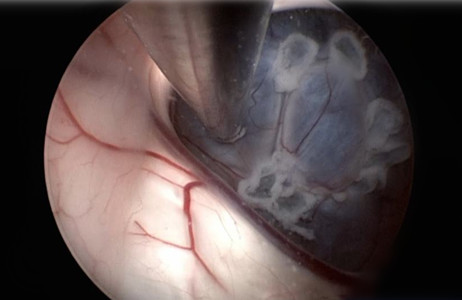

根据囊肿部位选择钻孔部位,注意避开静脉窦,内镜直接进入囊肿或经小脑半球皮质进入囊肿,其目的是沟通囊肿和周围脑池和(或)第四脑室。无需行囊壁全切除或大部分剥除,应尽可能的多处造瘘,瘘口应足够大,以提高手术的远期疗效。

囊肿-脑池造瘘术适合于邻近脑池的半球囊肿;囊肿-脑室造瘘术适合于紧贴脑室且不邻近脑池的半球囊肿,术中可同时行囊肿-蛛网膜下腔造瘘术,并尽可能切除游离的囊肿壁。